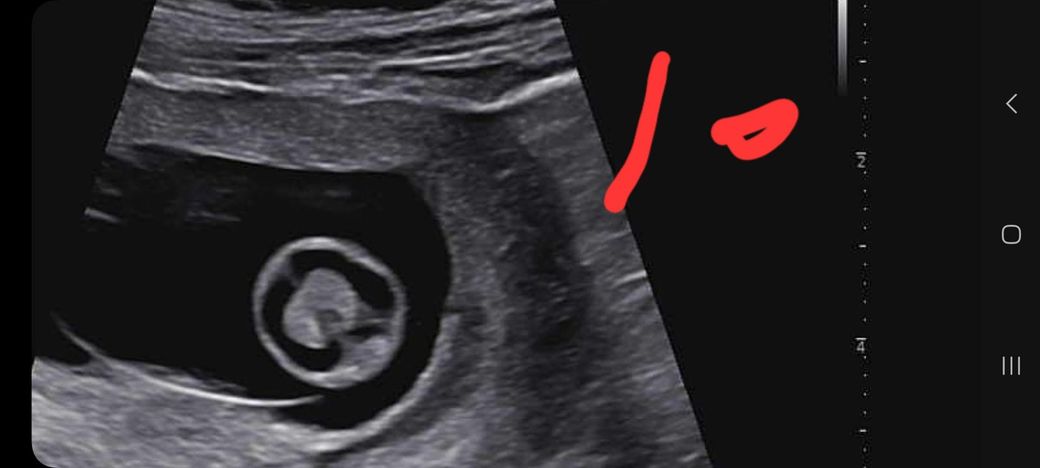

임신 12주차 태아 뇌 초음파 좀 봐주세요ㅜ

임신 12주차 이며 10주차 때 뇌 모양이 신경쓰인다고

12주차 초음파 때 다시 보자 하시더라구요

그래서 오늘 다녀왔는데

앞쪽(이마 쪽)이 신경 쓰인다며 소견서 써줄테니

대학병원 다녀와보라 하시네요ㅜ

사진 한번 보시구 이야기, 조언 좀 부탁드립니다.

(10주차 사진은 10이라 적었습니다.)

12주차 태아의 뇌는 양쪽이 대칭인 나비 모양을 띠는 것이 아주 건강하게 잘 자라고 있다는 신호예요.

초음파상으로 뇌실의 모양이 고르고 깨끗하다면 대부분의 경우 발달이 정상적으로 이루어지고 있다고 보시면 됩니다.

다만 초음파는 각도에 따라 다르게 보일 수 있으니 담당 선생님의 소견을 믿고 마음을 편히 가지시는 게 좋아요.